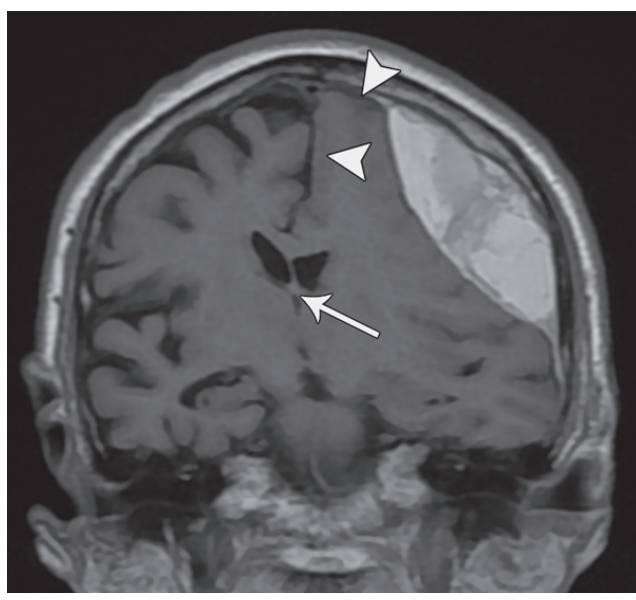

冠状对比增强 ct 图像显示大脑镰自由缘下方的扣带回从左到右突出